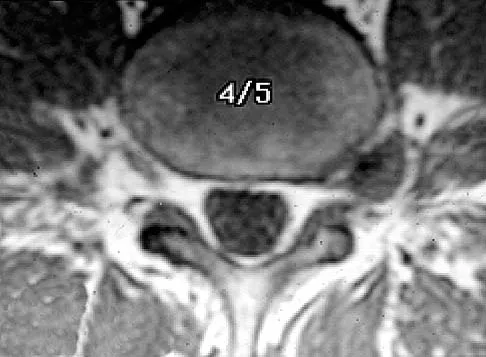

The MRI findings shown in Figure 51 would most likely create which of the following signs and symptoms?

Explanation

The MRI scan shows a far lateral disk herniation. With the L4-5 disk, a far lateral herniation abuts the left L4 nerve root. The findings would be consistent with those of a left L4 radiculopathy and would include pain or a sensory deficit on the anteromedial aspect of the knee, diminished patellar tendon reflex, and quadriceps weakness, perhaps making it difficult to walk up and down stairs. Fardin DF, Garfin SR (eds): Orthopaedic Knowledge Update: Spine 2. Rosemont, IL, American Academy of Orthopaedic Surgeons, 2002, p 329.